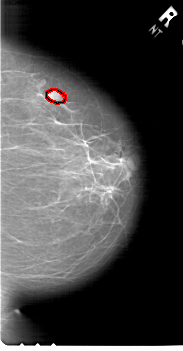

FILE: A_1765_1.RIGHT_MLO.OVERLAY

TOTAL_ABNORMALITIES 1

ABNORMALITY 1

LESION_TYPE MASS SHAPE OVAL MARGINS OBSCURED

ASSESSMENT 4

SUBTLETY 4

PATHOLOGY BENIGN

TOTAL_OUTLINES 1

BOUNDARY